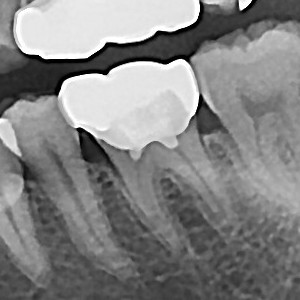

충치치료&신경치료 하루에 끝나는 신경치료

c36d6f431fa4d39e6efca10cb66686a2_1767329043_0796.jpg